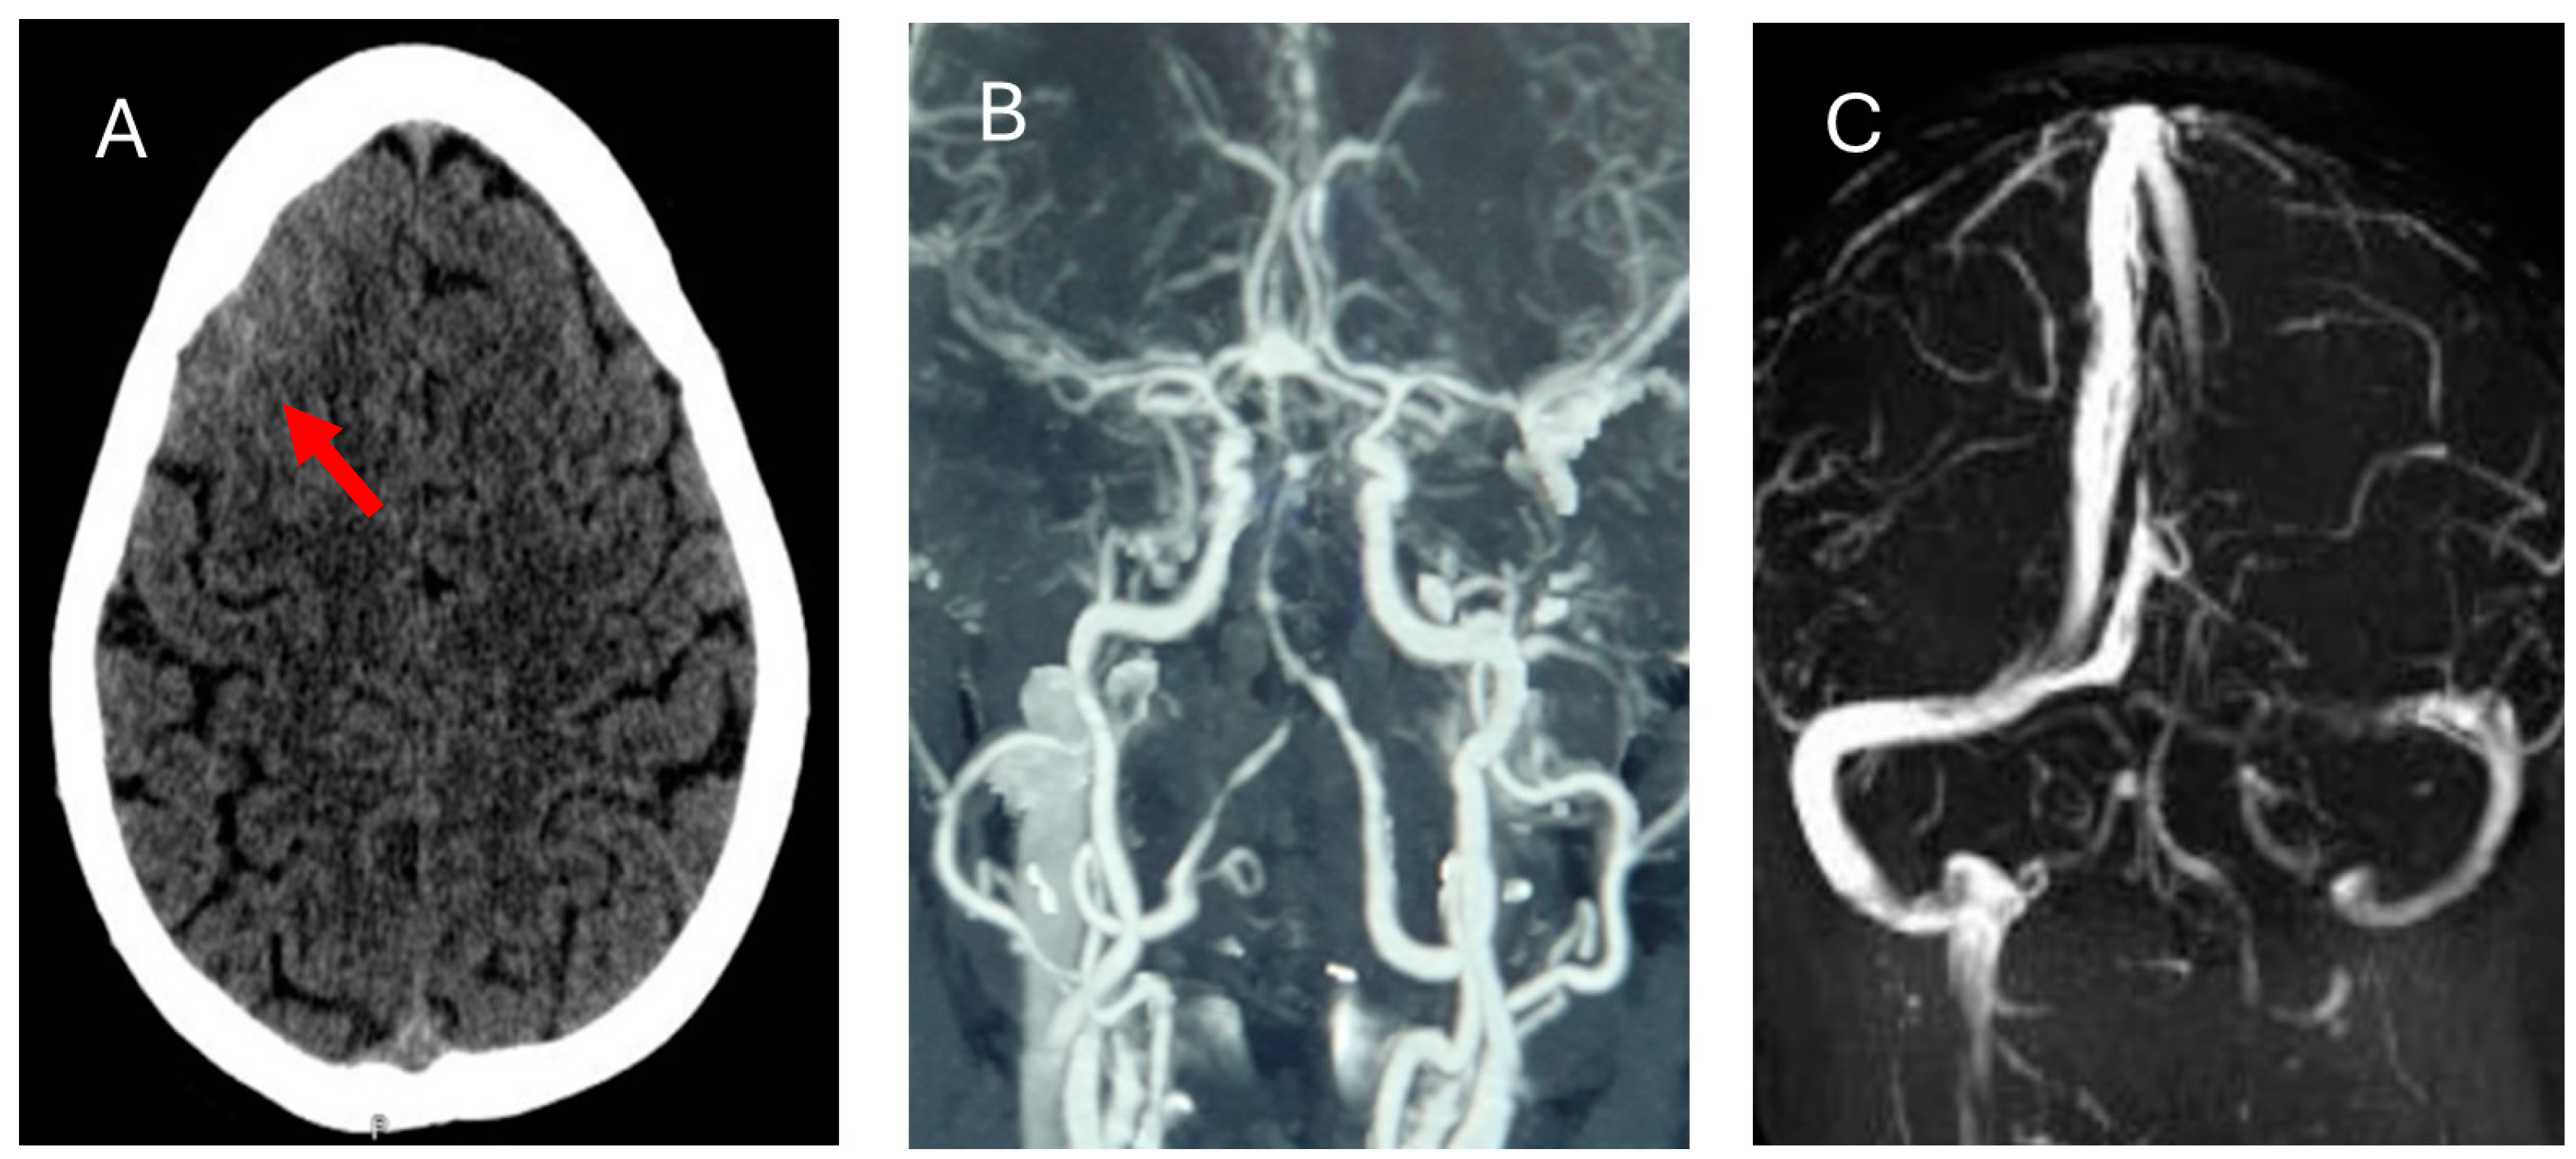

2. Case Presentation